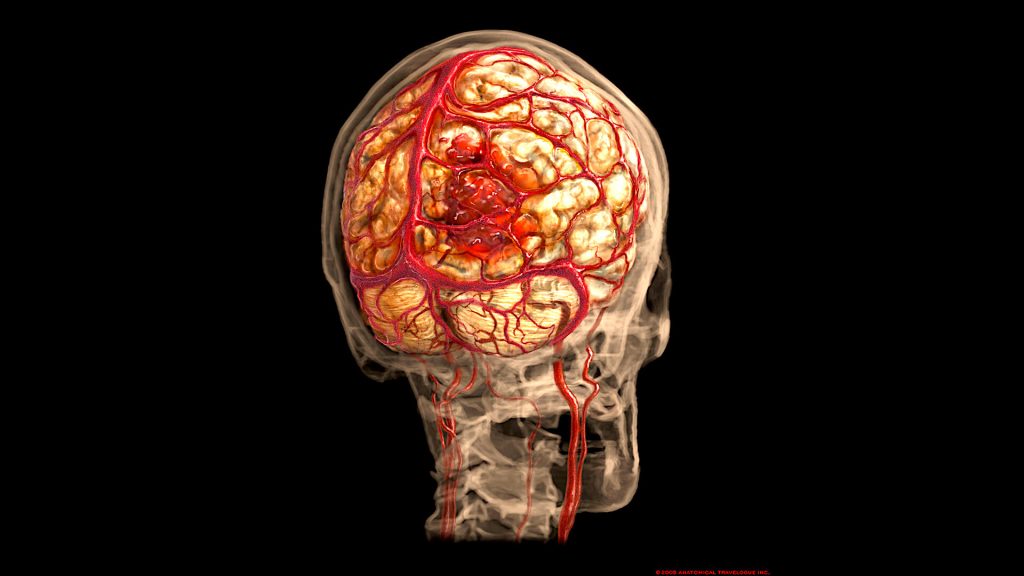

Porencephaly is a rare neurological disorder characterized by cysts or cavities within the brain’s cerebral hemispheres. These fluid-filled spaces can affect brain function depending on their size and location. Porencephaly can be congenital (present at birth) or acquired after brain injury.

- Imaging studies: MRI and CT scans reveal cystic cavities in the brain